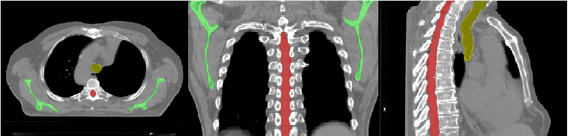

The geometric validation is an initial test of the ability of the registration tool to map matching anatomical features between the images. To validate the registrations geometrically, three sample structures—the scapulae, spinal canal and trachea—were directly outlined on both the pCTs and CBCTs for each patient in accordance with clinical protocols. These particular structures were chosen because they were easily identifiable on the CBCT images (figure 2).

Figure 2. Scapulae (green), spinal canal (red) and trachea (yellow) as outlined on the pCT for a single patient.

Download figure:

Standard image High-resolution imageThe pCT structure sets were then deformed by applying the transformation obtained from the optimised registrations. Deformed structures were cropped to match the CBCT structures in length where necessary.